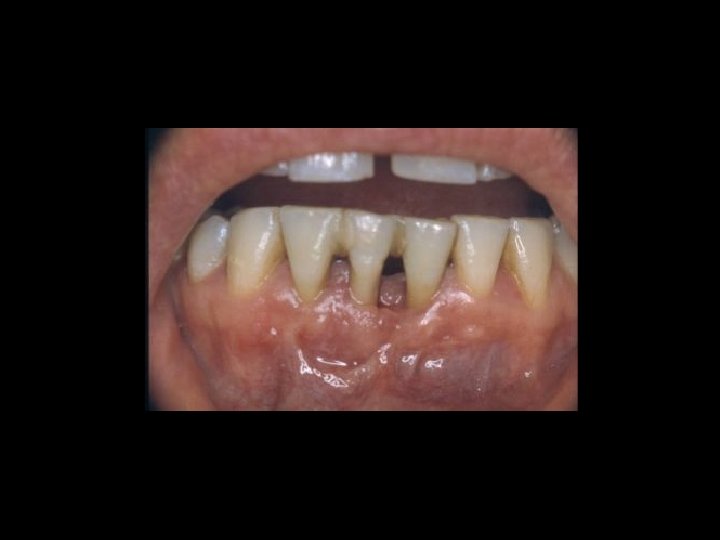

Responsabilità Ø Restauro della corona del dente Ø Trattamenti radicolari